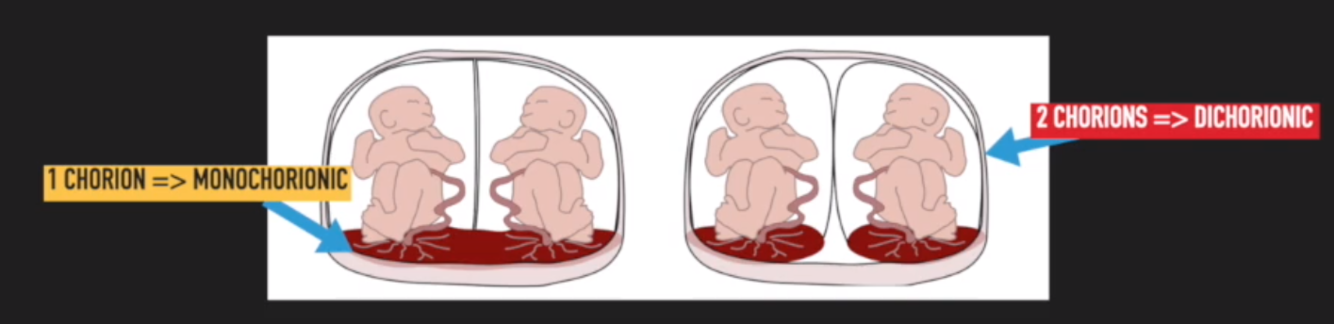

What is chorionicity?

Chorionicity = number of chorionic (outer) membranes that surrounds foetus in a multiple pregnancy:

- If there is 1 membrane, monochorionic

- If there are 2 membranes, dichorionic